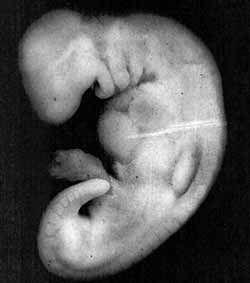

Figure 5: Photograph of an embryo at the mudghah stage (28 days old).  The embryo at this stage acquires the appearance of a chewed substance, because the somites at the back of the embryo somewhat resemble teeth marks in a chewed substance.  The actual size of the embryo is 4 mm. (The Developing Human, Moore and Persaud, 5th ed., p. 82, from Professor Hideo Nishimura, Kyoto University, Kyoto, Japan.)

Figure 5

The next stage mentioned in the verse is the mudghah stage.  The Arabic word mudghah means “chewed substance.”  If one were to take a piece of gum and chew it in his or her mouth and then compare it with an embryo at the mudghah stage, we would conclude that the embryo at the mudghah stage acquires the appearance of a chewed substance.  This is because of the somites at the back of the embryo that “somewhat resemble teethmarks in a chewed substance.”6 (see figures 5 and 6).